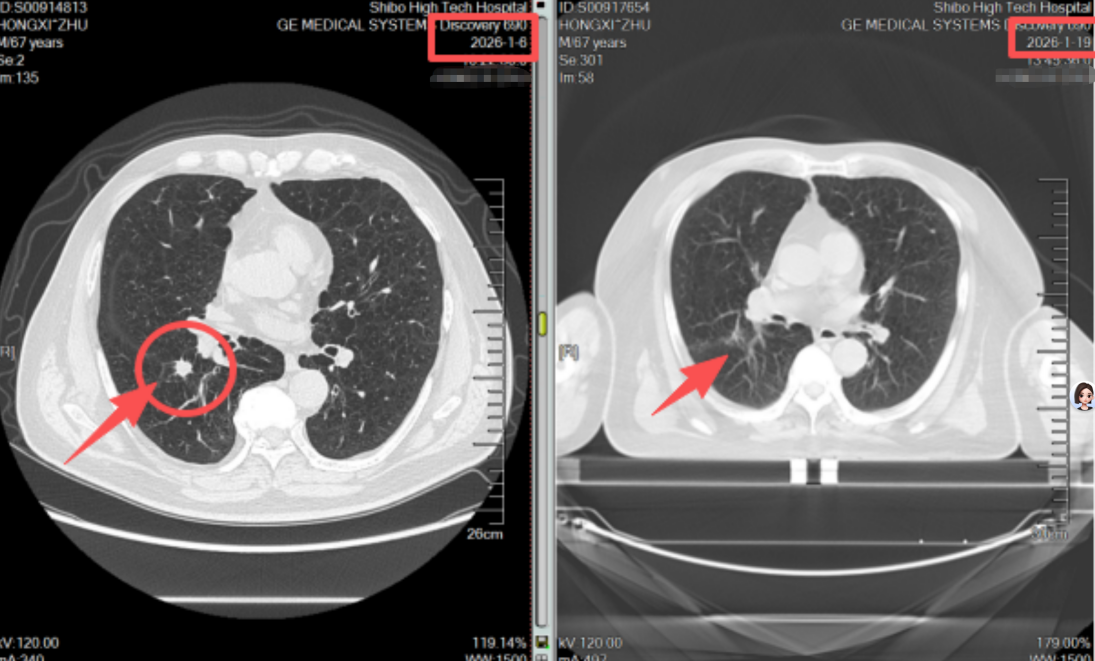

不同于传统放疗需数十次照射、持续一两个月,患者需要数次的射波刀治疗,全程无切口、无出血、无需麻醉,每次治疗约30分钟,结束后即可自主离院。治疗两周后复查CT,影像结果显示:原本的肺结节病灶基本消失,周围正常肺组织无任何损伤,患者身体状态良好,无明显不适症状。